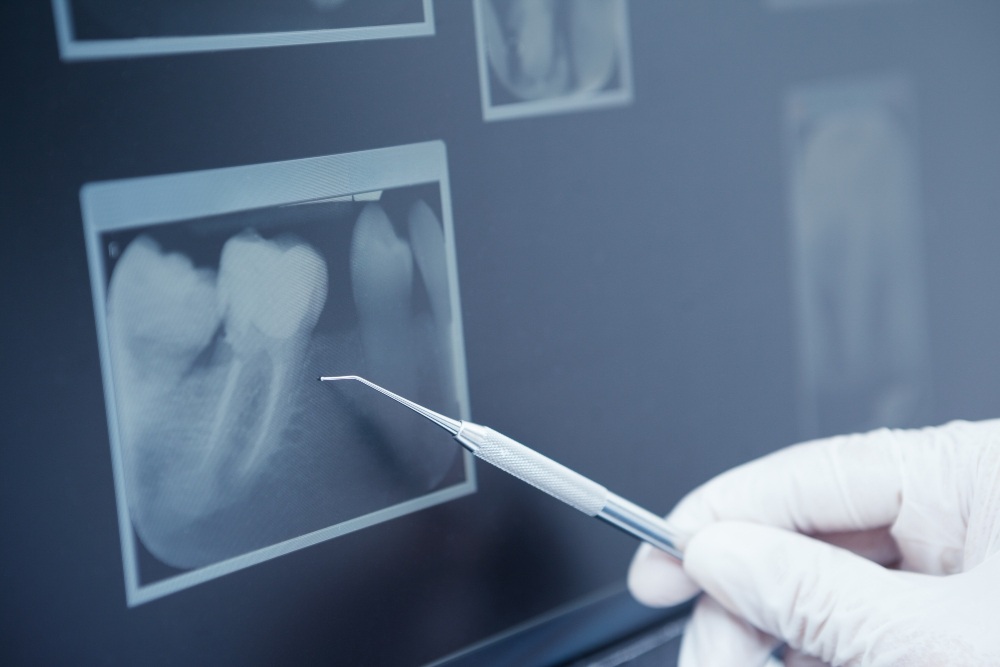

Dental X-rays are diagnostic images that allow your dentist to see what is happening beneath the surface of your teeth, gums, and jawbone. They help in detecting:

- Cavities between teeth

- Bone loss

- Impacted teeth (like wisdom teeth)

- Infections or cysts

- Root canal complications

- Jawbone issues

These show the upper and lower back teeth in one image. Dentists use them to detect decay between teeth and monitor bone levels.

These focus on just one or two teeth from the crown to the root. They help detect root issues, abscesses, or bone loss.